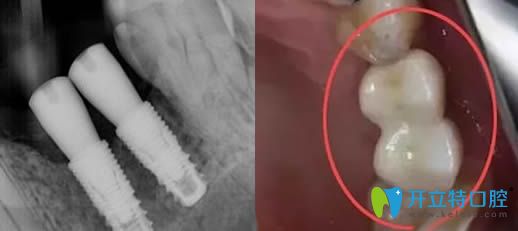

種植體種歪了的效果圖片

所以種植體歪了大家也不要過分擔(dān)心,并不全是種植失敗了。但如果歪斜較重,只能重新種植了,?因為傾斜角度過大,則會造成承受咀嚼的側(cè)向力過大,從而造成種植失敗的。

因此,對于輕微傾斜的植體,在安裝牙冠時,醫(yī)生會通過角度基臺來調(diào)整角度,這樣后期牙冠是整齊的,但植體的歪斜是不可逆的。

種植體歪了可以做牙冠調(diào)整修復(fù)